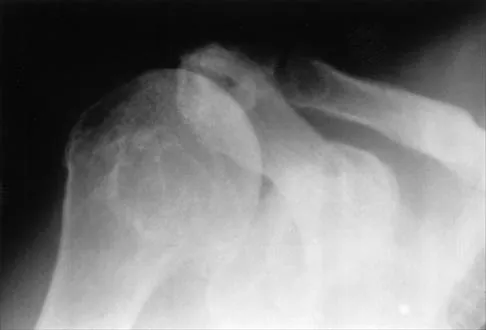

Master AAOS & ABOS boards with 2026 practice MCQs (Set 1), covering shoulder instability, rotator cuff pathol…

Prepare for AAOS & ABOS boards with Orthopedic MCQs (Set 1). This comprehensive review covers high-yield ques…